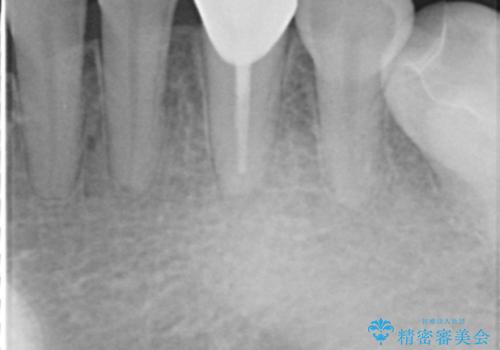

CTでみたところ、下の犬歯が内側に倒れこんでおり、根の先が顎の骨から出かかっている状態でした。おそらくその影響で犬歯の神経が失活してしまったのであろうと思われます。(フェネストレーションといいます)

検査した結果下の両側の犬歯の神経が失活しており、根の治療が必要な状態でした。

- 57.2万円 内訳:下顎左右犬歯 再根管治療 9万円x2本 ファイバーコア 2万円x2本 仮歯 1万円×2本 ジルコニアクラウン(スペシャル) 13万円×2本費用は治療当時の料金となります

一見歯がきれいに並んでいても、中の根の先の位置までしっかり矯正治療で丁寧に動かさないと、今回のように神経が失活するリスクがあるので、注意が必要です。